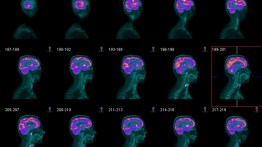

In the cult Steve Martin film The Man With Two Brains, a doctor falls in love with a surgically removed brain. The object of his desire (fizzing, if I remember rightly, in a demijohn of formaldehyde) makes for an enduring gothic comedy of the mind. On the movie’s release in the early 1980s, neuroscience was still in its infancy. Men in white coats were cutting up monkey brains and their laboratories smelled of monkey urine. In recent years, however, neuro-imaging has changed the study of the human mind completely. Rainbow-coloured images on the scanner screen reveal our most precious and mysterious organ in all its alien complexity. Computer imaging may